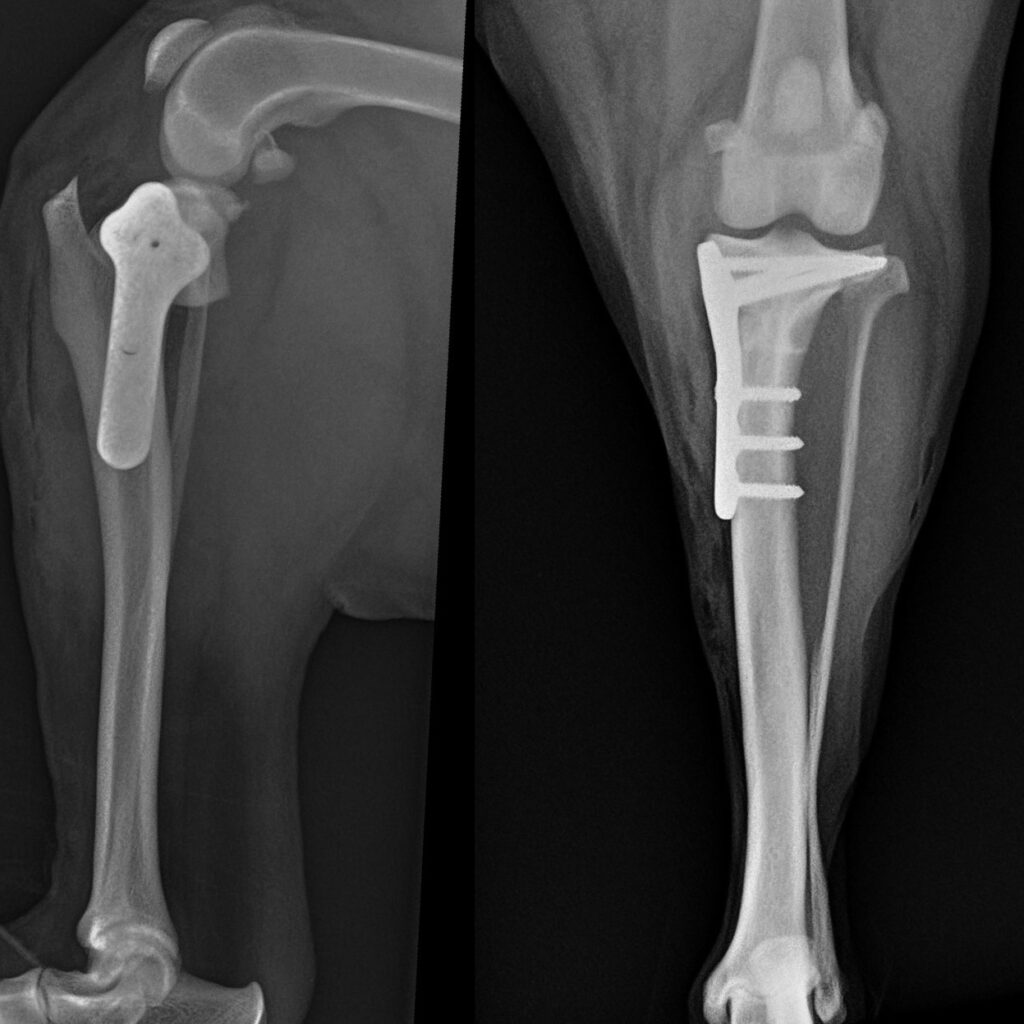

Orthopaedic surgery, we are able to repair fractures, operate in joints, perform arthroscopy, etc. below you can find a list of prices for the most common procedures (the prices include all that your pet will need in the day like blood tests, radiographs, surgery, medications, and also the medications that we routinely send them home with)

| Tibial plateau levelling osteotomy (TPLO) <25kg | £2500 |

| Tibial plateau levelling osteotomy (TPLO) 25-40kg | £2800 |

| Tibial plateau levelling osteotomy (TPLO) >40kg | £3200 |

| Simple fracture repair requiring only pins and tension bands | £1500-£2000 |

| Simple fracture requiring metal plate | £2000-£3000 |

| Complex fractures | £2500-£4000 |